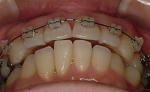

CASE2

↓前歯の歯並びを きれいに治したい。

(35歳/女性)

|||||||||

概要・担当医コメント:叢生・審美障害↑

動的治療期間13ヶ月(12回)/非抜歯/費用概算:55万円

上は固定式のブラケット矯正で,下は患者様ご自身が着脱するマウスピース矯正の治療を行いました.治療結果には大変満足されているそうです.